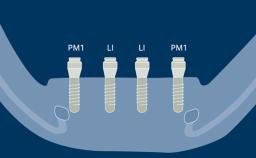

Once an implant is placed, there are three loading protocols that may be used. An implant loading protocol is defined as the time elapsed between implant placement and the attachment of the prosthesis so that the implant is brought into function.

Conventional loading of dental implants is defined as loading 2 or more months after implant placement. This is a well-established protocol that allows for complete healing of bone and peri-implant soft tissues prior to prosthesis attachment.

In an early loading protocol, the prosthesis is attached between 1 week and 2 months subsequent to implant placement. The implants are put into function during the later stages of bone healing but prior to complete healing of soft tissues. This results in a relatively reduced treatment time between implant placement and loading compared to the conventional loading protocol.

In contrast, immediate loading of dental implants is defined as prosthesis attachment within 1 week of implant placement, including the day of surgery. In this case, the process of peri-implant bone and soft tissue healing occurs with the provisional prosthesis attached to the implant from the outset.